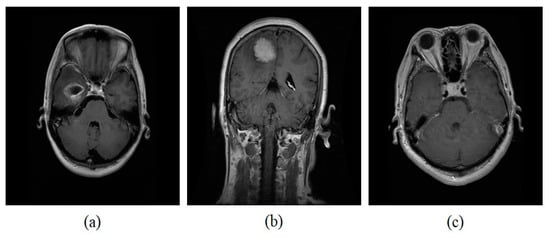

We use a publicly available brain MRI dataset called Figshare developed by Cheng et al. [38]. The dataset contains 3064 T1-weighted brain MRI slices of three different categories of tumor for example meningioma, glioma, and pituitary obtained from 233 patients. The dataset comprises 708 meningioma slices, 1426 glioma slices, and 930 pituitary slices. All images are stored in .mat format. The MRI slices are normalized with an intensity range between 0 to 1. Figure 2 shows three categories of brain tumors from the Figshare dataset. Figure 3 demonstrates the images obtained after the application of the data augmentation technique.

Figure 2. Sample brain tumor dataset from Figshare (a) Glioma (b) meningioma (c) pituitary.

Processes 11 00679 g002